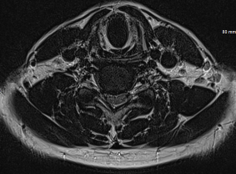

그림4.png 촬영 일시: 2025.04.30

<Fig 2. 경추 PEN 시술>

시술 직후부터 변화가 있었어요.

그분이 하신 말씀이

"뭔가 오래 눌려 있던 게 풀리는 기분이에요" 였거든요.